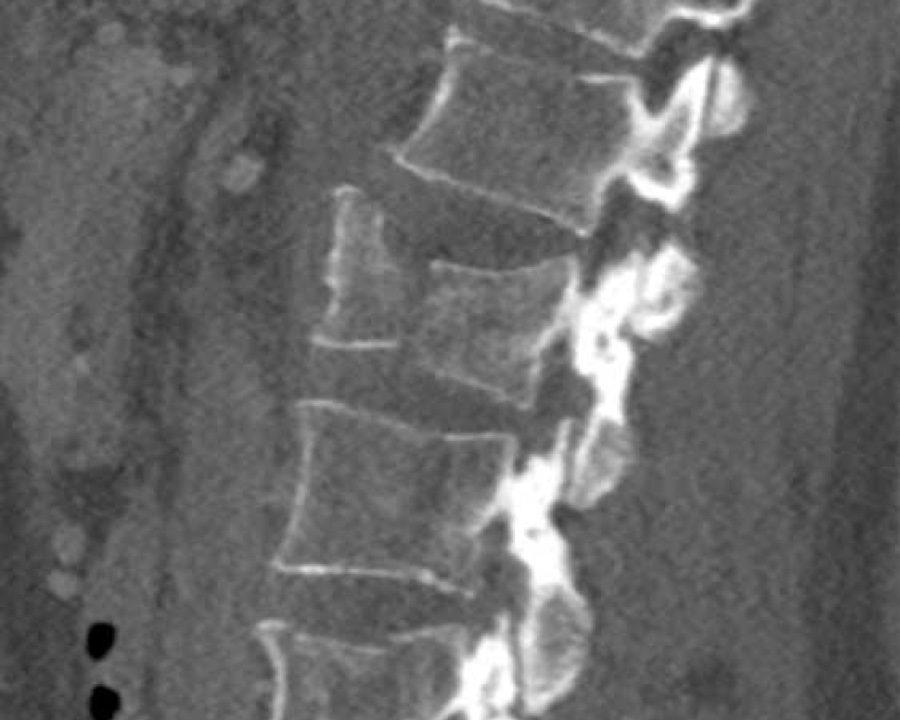

What is the AO-type of the vertebral body fracture based on only these two inages?

Findings:

- Fractures of the vertebral body with involvement of upper endplates (1 points) and posterior wall (2 points)

- Bulging of the posterior wall without any other signs of dislocation is the result of the burst fracture.

Therefore no C injury.

Conclusion

Injury type A3